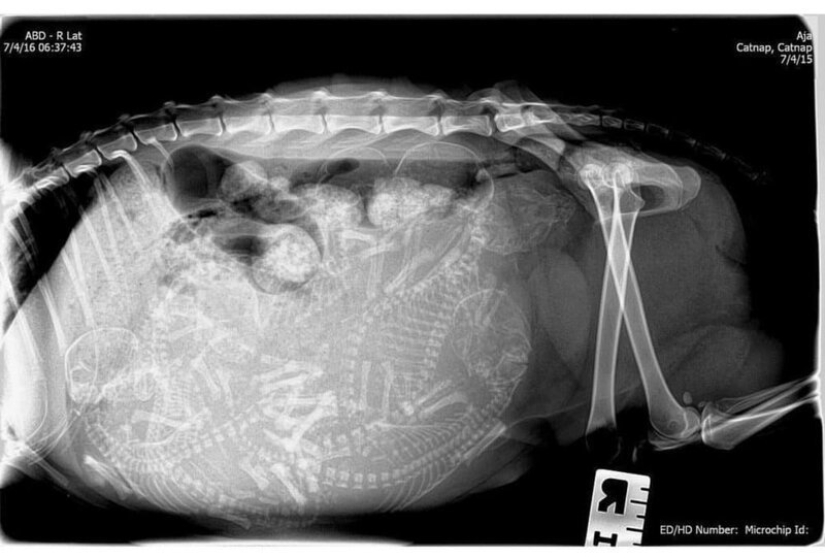

Quién vive en la casita: radiografías de animales preñados

Por Pictolic https://pictolic.com/es/article/quien-vive-en-la-casita-radiografas-de-animales-prenados.html¿Alguna vez te has preguntado qué sucede en el útero de una gata o una perra preñada? ¿Cómo encajan todos estos pequeños bebés allí y logran desarrollarse durante todo el embarazo? La mayoría de los animales preñados se examinan mediante rayos X. Y éstas, cabe señalar, son fotografías muy interesantes.

Especialistas que como parte de su trabajo observan animales que están listos para parir, compartieron estas sorprendentes imágenes de rayos X y ultrasonido.

gata preñada